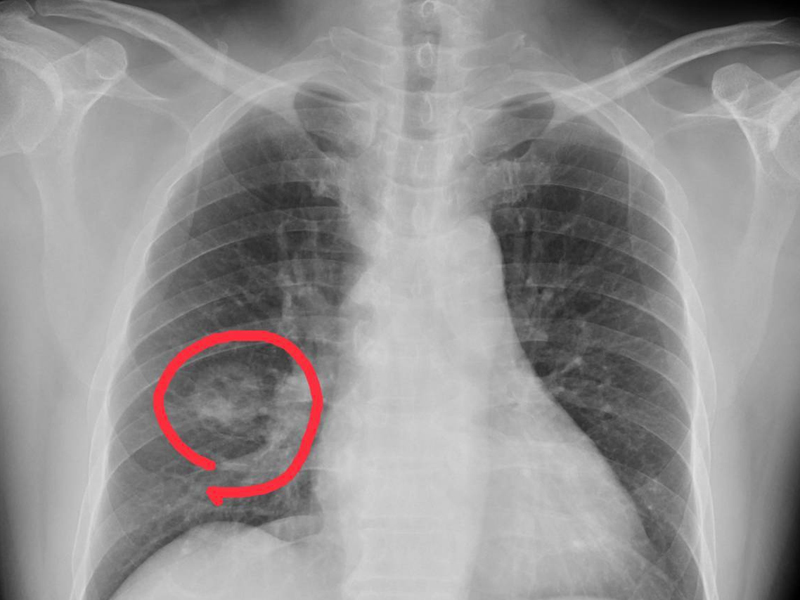

瀏覽:16907 手腳出現 4 種異常,可能是得肺癌了,千萬不要大意 | 瀏覽:2555 耶鲁研究揭示,輝瑞疫苗後遺症 | 瀏覽:2516 每個人體內都有癌細胞,為什麼有人卻不會得癌 |